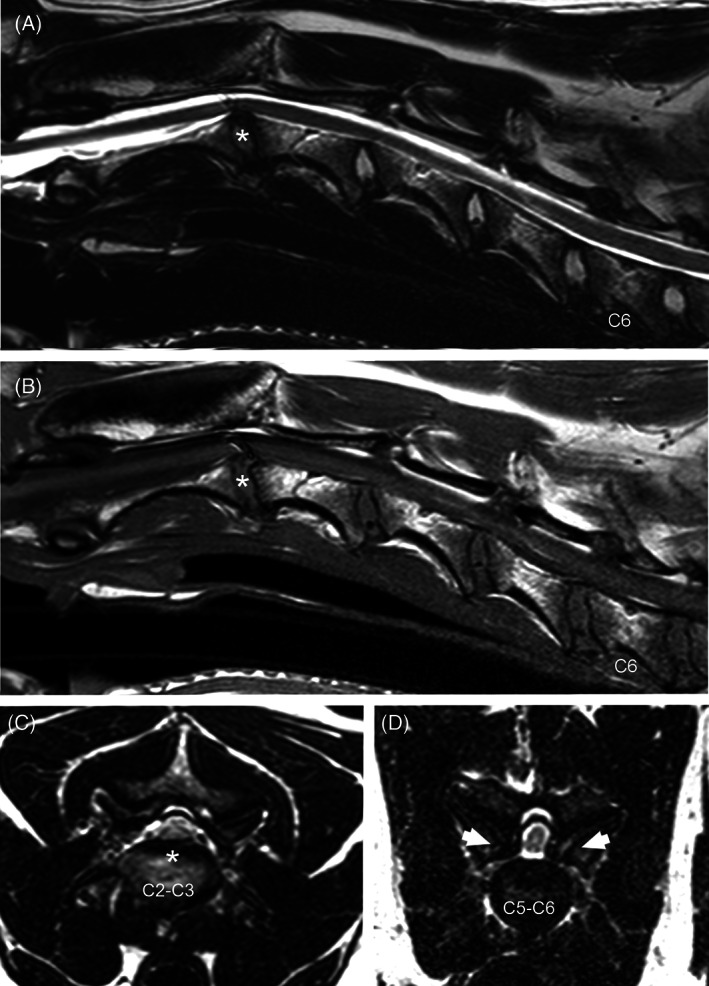

FIGURE 1.

Sagittal T2 (A) and T1‐weighted (B) and transverse T2 (C) and T1‐weighted (D) MR images from a 6‐year‐old Bernese Mountain dog with C5‐C6 ventrodorsal and C6‐C7 ventral compression with spinal cord hyperintensity at both sites. The ventral component is intervertebral disc protrusion (arrows) and the dorsal component is ligamentum flavum/soft tissue hypertrophy and dorsal lamina thickening (asterisk). There is also osseous proliferation of the articular processes seen on transverse images (C, D). Absent joint fluid can be seem at the right articular process joint and reduced joint fluid on the left articular process joint (C—open arrowheads). Subchondral bone of the articular processes was classified as smooth with signs of subchondral sclerosis bilaterally (D—open arrowheads).